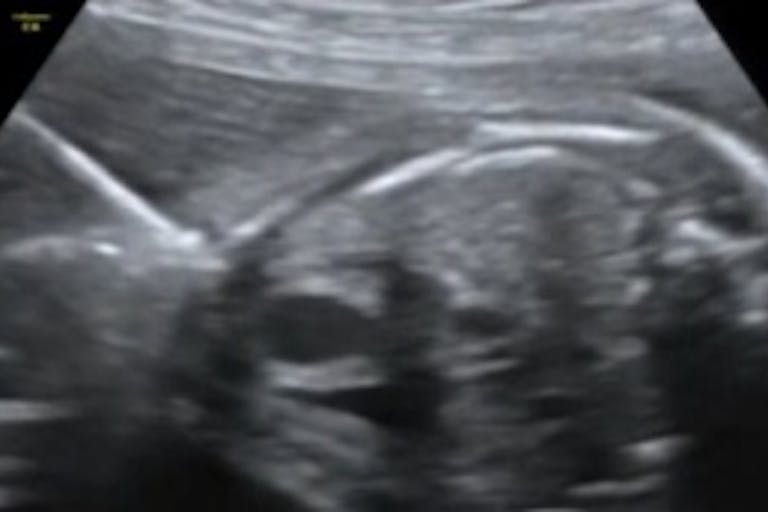

This video shows a clip of the ultrasound used during the surgery, during which doctors inserted a tiny tube and inflated a balloon into the baby’s heart to open up the poorly-functioning valve. To prepare for the highly specialized surgery, doctors practiced on a grape (representing the baby’s heart, which is about the size of a walnut at 25 weeks gestation) inside of Jello, which represented the baby’s body surrounding the heart.